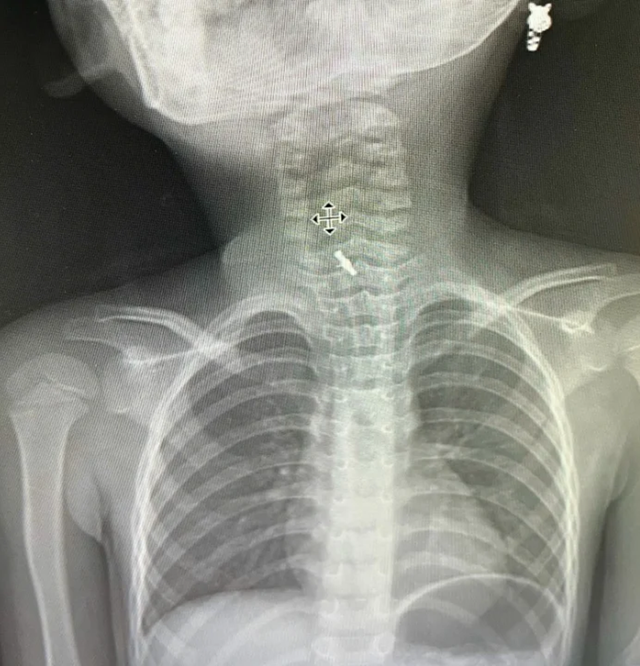

Tại viện sau khi thăm khám và chụp chiếu, hình ảnh chụp phim X-quang cho thấy bệnh nhi có dị vật mắc sâu trong thực quản. Các bác sĩ đã thực hiện nội soi bằng ống cứng và gắp dị vật ra ngoài.

BSCKI Bế Thị Minh Quỳnh, Khoa Chẩn đoán hình ảnh cho biết: "Dị vật được lấy ra là một chiếc kẹp tóc nhựa, có nhiều góc cạnh, nên việc gắp dị vật ở trẻ em đòi hỏi phải cực kỳ cẩn trọng. Nếu không cẩn thận, dị vật có thể làm rách niêm mạc, chảy máu, thậm chí thủng thực quản. Do đó, quy trình này cần sự phối hợp chặt chẽ của cả ê-kíp chuyên môn".